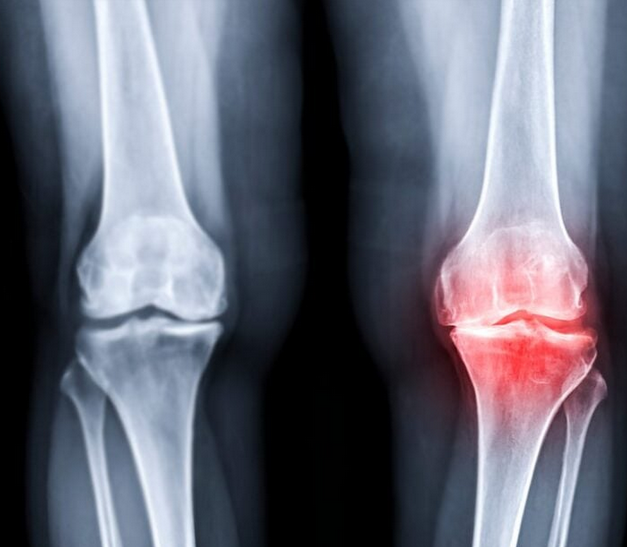

Key Differences Between Osteoarthritis and Rheumatoid Arthritis

Cause

- Osteoarthritis: mechanical wear and joint degeneration

- Rheumatoid arthritis: autoimmune inflammation

Joint Involvement

- Osteoarthritis: often affects one joint or one side

- Rheumatoid arthritis: usually symmetrical